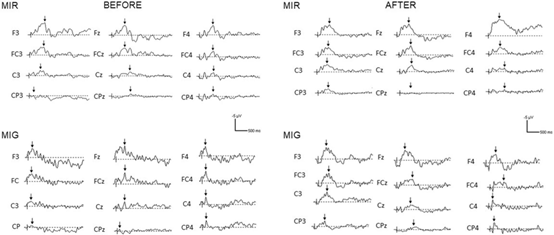

在选定的电极和测量阶段(前后),在达到运动想象(MIR)和抓取运动想象(MIG)期间ERP的个体模式。垂直线表示触发器发生的时间,箭头表示ERP振幅。

研究发现,MIT对与伸手相关的脑电图信号的影响不同于抓取,MIR的效果比MIG更明显。结果表明,由于MIT引起的评估参数的变化降低了想象主观评价与EEG信号之间的关系。

这种效应在“伸手”的想象上比“抓住”的想象上更为明显。在两个任务和会话中,前运动皮层上方的电极的ERP振幅都高于感觉运动皮层。并且,使用依赖的MIR和MIG能力的变化,以及在这些任务中的皮质活动(就ERP而言)改变了两者之间的相关性。因此,想象任务的应用主观评价不能是对心理训练过程中ERP所表达的大脑皮层生物电活动的简单的功能性洞察。这些发现与神经康复和心理训练的目标导向达成有关。训练后ERP的变化可能有利于非侵入性脑电图在BCI背景下的使用。